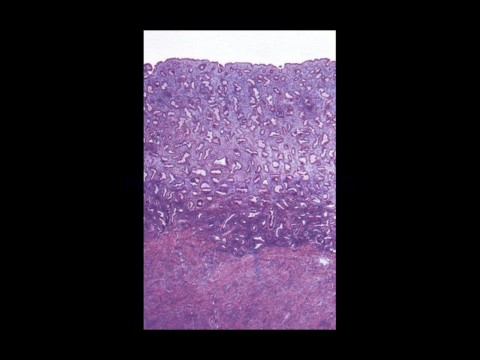

Page 73 - KADIN ÜREME SİSTEMİ

Prof. Dr. Canan HURDAG